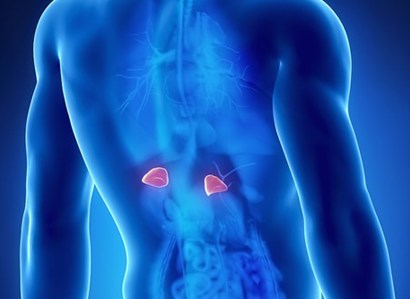

The adrenal glands are two very small but vital endocrine glands. Issues with the adrenal glands are treated as part of endocrinology.

Read Adrenal disease Article